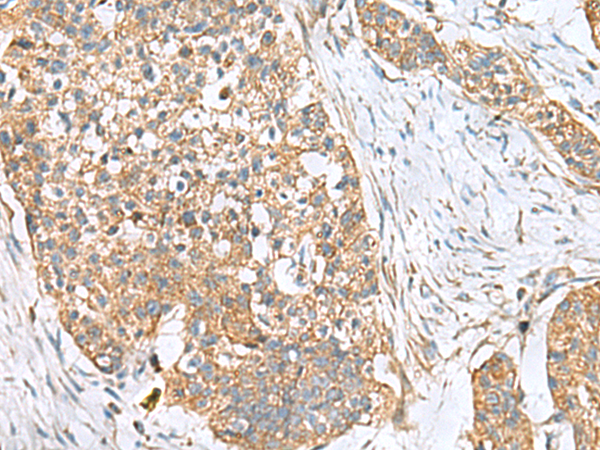

IHC (Immunohiostchemistry)

(The image is immunohistochemistry of paraffin-embedded Human esophagus cancer tissue using AAA310795 (CEMIP Antibody) at dilution 1/120.(Original magnification: AS200))